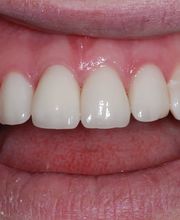

Das Bodensee Implantat Zentrum (ZIP) ist Ihre führende Praxis für Zahnheilkunde in der Region. Wir sind spezialisiert auf hochwertige Implantologie, einschliesslich des All-on-4® Konzepts, für das wir als Excellence Center Gold-zertifiziert sind. Unser Leistungsspektrum umfasst Komplettsanierungen, Kronen, Brücken sowie ästhetische Behandlungen. Mit über 30 Jahren Erfahrung bieten wir auch Angstpatienten eine einfühlsame Betreuung und Behandlungen unter Narkose für ein strahlendes Lächeln.